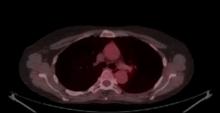

A 59-year-old woman underwent an examination for amaurosis fugax. A chest CT scan revealed a 2.6 cm tumor in the apex of the left upper lung attached to the chest wall. Since this lesion was considered highly suspicious for cancer, the patient underwent a PET scan that showed a hypermetabolic nodule with a SUVmax of 17.6. There were no hypermetabolic hilar or mediastinal lymph nodes, or distant metastasis. After a complete preoperative work-up with spirometry and a cardiopulmonary stress test, the patient was considered for a left upper lobectomy.